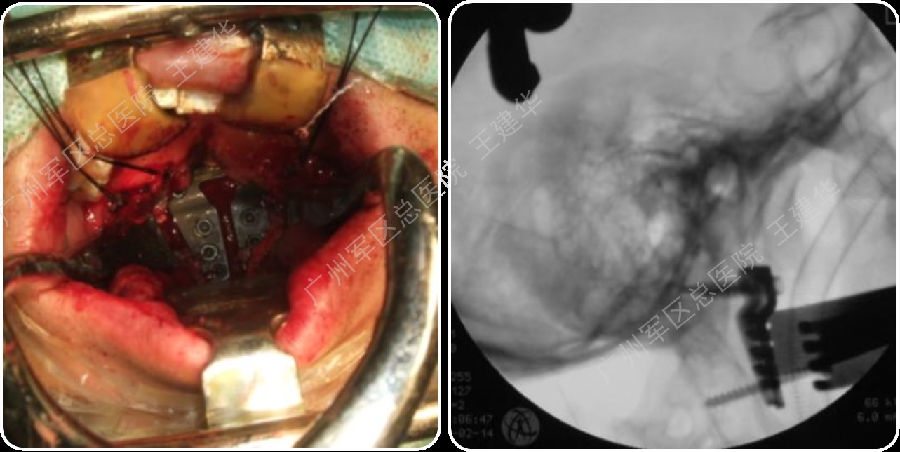

本例患者手术过程

手术复位过程

手术完成

手术前后对比

可以看到:

陷入枕骨大孔的寰椎和齿突已经下拉复位,枕颈排列恢复正常